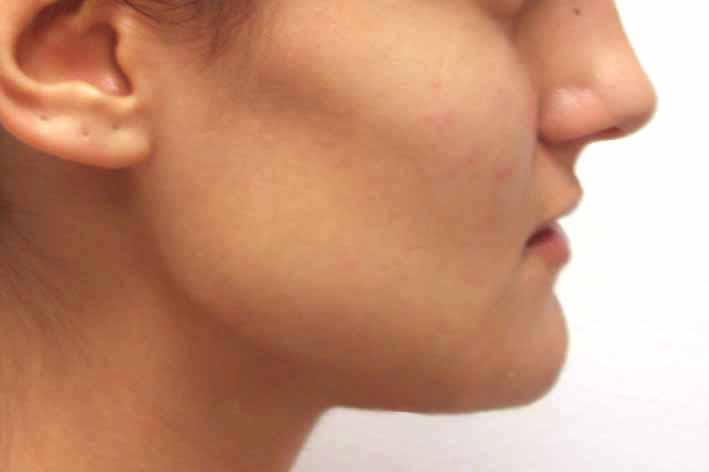

В процеса на стареене се задълбочават челните бразди, западат веждите, отпускат се клепачите, загубва се окръглената форма на бузите и се появяват хлътнали линии по шията. Операциите, за корекция на тези процеси, са блефаропластика (корекция на клепачите), повдигане на челото и веждите (фейс-лифт), септоринопластика (корекция на носа и носната преграда), отопластика (корекция на ушите), ментопластика (корекция на брадата) и др.

Корекция на брадата преди и след лечението – случай на доц. Джоров